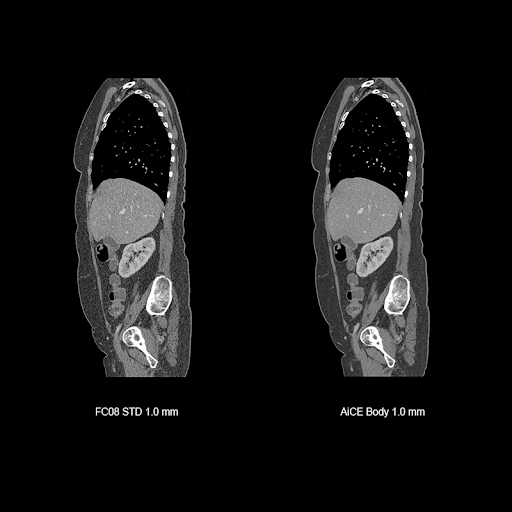

Визуализация органов грудной полости, живота и малого таза

Визуализация опорно-двигательного аппарата